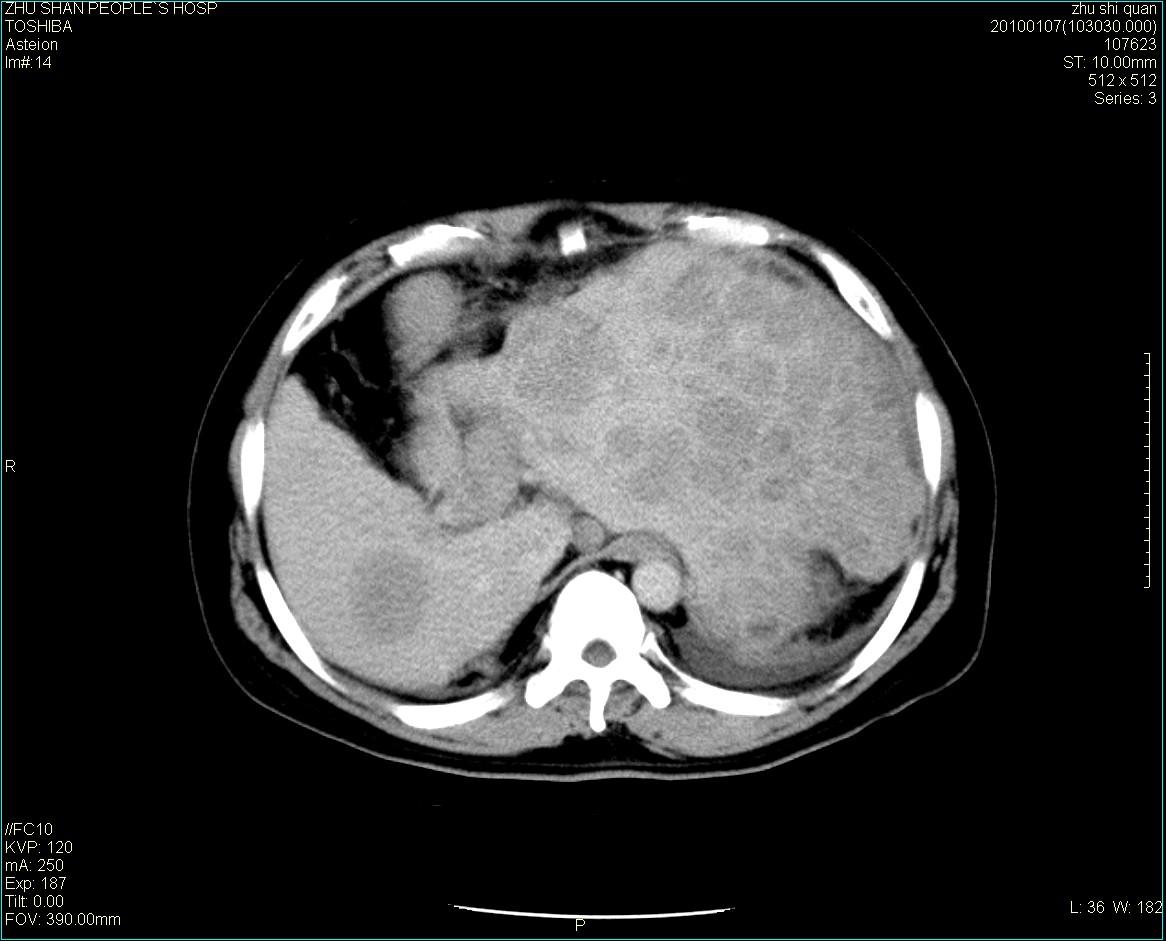

男性病人 肝ca两次术后,今日复查。

多发转移

肝、脾多发转移灶,胸腔积液

多发转移灶

1)肝癌并多发性转移。2)双侧胸腔积液(以左侧为甚)伴左下部分肺萎陷。

肝癌术后复发,考虑肝、脾多发转移。

肝癌术后复发,肝内、脾脏、腹膜后及腹膜多发转移,腹水,双侧胸腔积液(以左侧为甚)伴左下膨胀不全。

肝、脾多发转移灶,胸腔积液。

肝癌术后复发,肝内、脾脏、腹膜后及腹膜多发淋巴结转移,腹水,双侧胸腔积液。